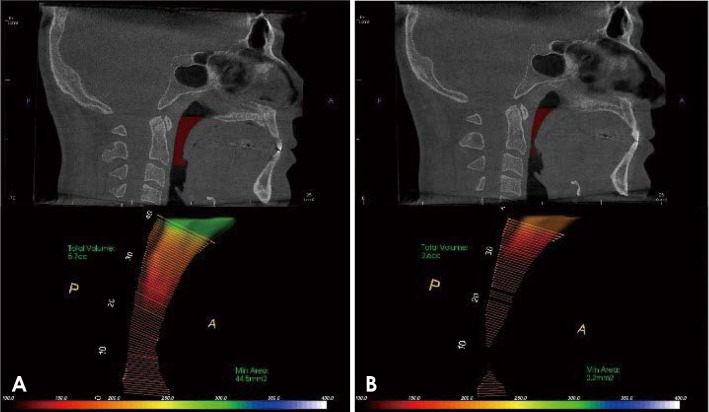

Materials and methods: Forty patients with obstructive sleep apnea were selected from the ear-nose-throat (ENT) outpatient clinic, Faculty of Medicine, Mansoura University. Cone-beam computed tomography was performed for each patient at the end of both inspiration and expiration. Polysomnography was carried out, and the apnea-hypopnea index was obtained. Linear measurements, including cross-sectional area and the SNA and SNB angles, were obtained. Four oral and maxillofacial radiologists categorized pharyngeal and retropalatal airway morphology and calculated the airway length and volume. Continuous data were tested for normality using the Kolmogorov-Smirnov test and reported as the mean and standard deviation or as the median and range. Categorical data were presented as numbers and percentages, and the significance level was set at P<0.05.

Results: The minimal value of the cross-sectional area, SNB angle, and airway morphology at the end of inspiration demonstrated a statistically significant association (P<0.05) with the apnea-hypopnea index, with excellent agreement. No statistically significant difference was found in the airway volume, other linear measurements, or retropalatal airway morphology.